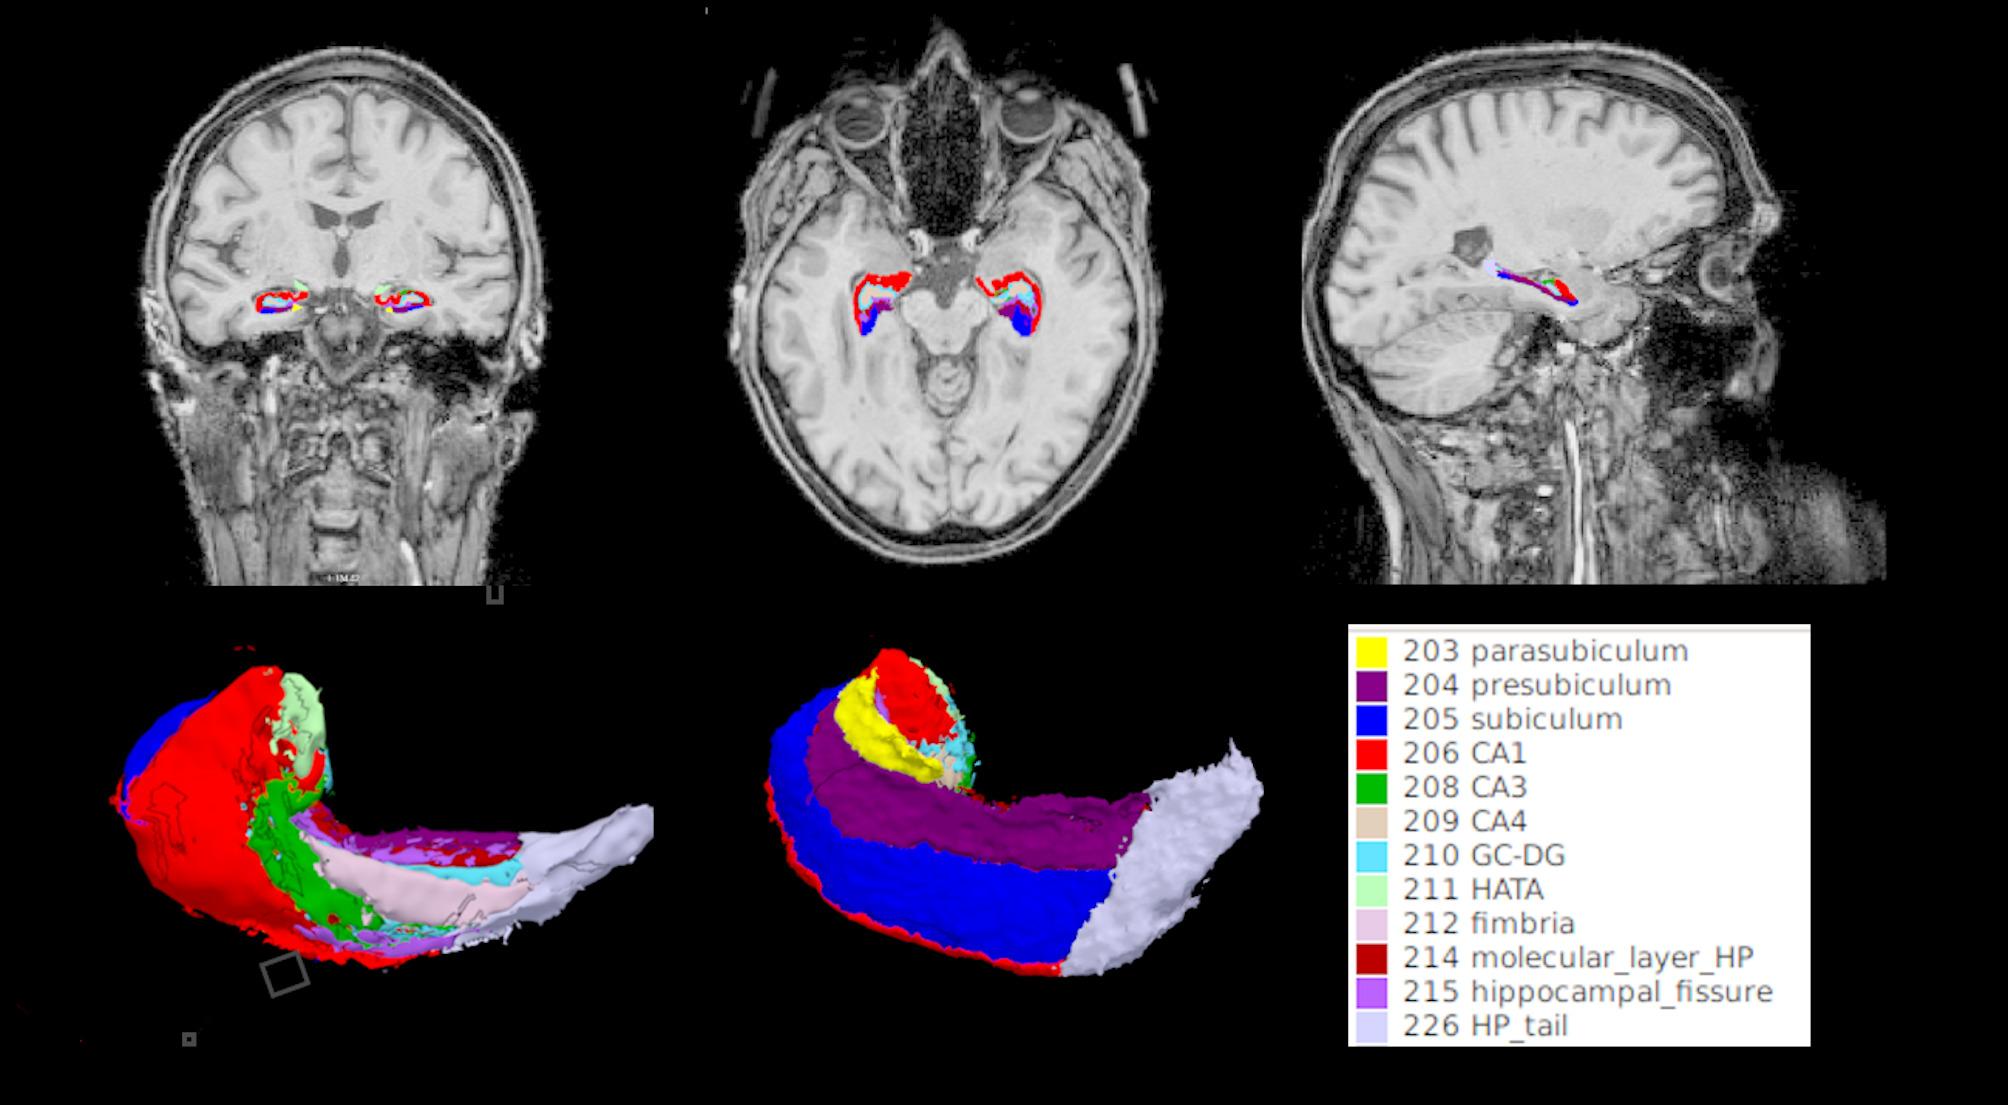

Objective: We investigated the utility of a LTR paradigm in discriminating subjective cognitive decline (SCD) from HC and its relationship to the CA1 body volume, a hippocampal structure pivotal to the memory circuitry.

Methods: LTR was assessed via recall rates of the ADAS-cog word list and the FCSRT-IR free recall in 59 DELCODE study participants, including individuals with SCD and mild cognitive impairment (MCI), as well as HC, all of them DELCODE study participants. LTR performance was compared between groups and its discriminability between SCD and HC was assessed using ROC curve analysis. 32 SCD and HC participants had FreeSurfer-segmented MRI data, and hippocampal subfield volumes were correlated with LTR rates.

Results: Only FCSRT-IR LTR rates sufficiently differentiated SCD from HC (AUC of 0.701; 95% CI 0.537-0.865). Moderate associations of the FCSRT-IR LTR rate with CA1 bodies in both hemispheres (left CA1 body r = 0.419, p = 0.017; right: r = 0.412, p = 0.019), in addition to the left C3 body were observed (r = 0.525, p = 0.002).